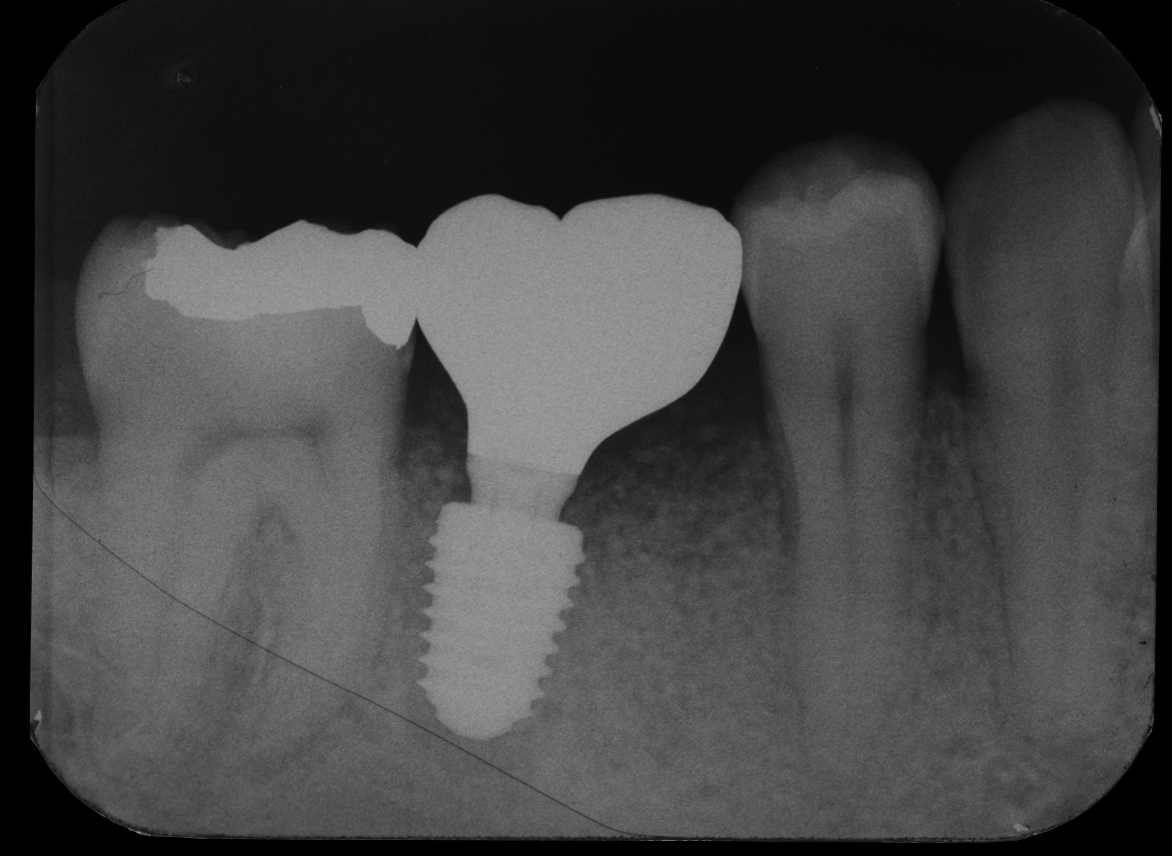

- After

オペから8週でセラミックの歯の型取りをします。炎症を起こして吸収してしまった骨も治癒してきています。

オペから10週後、セラミックの歯をセットして、治療は完了です。